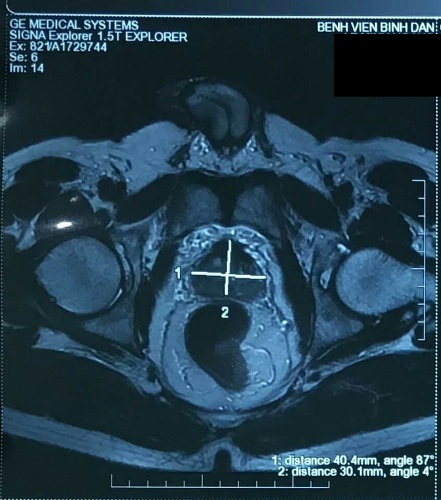

Khi chẩn đoán, kết quả chụp cộng hưởng từ MRI cho thấy khối u choán chỗ vùng ngoại biên nhưng chưa xâm lấn túi tinh ở tuyến tiền liệt của bệnh nhân quê ở Bình Phước. Kết quả xạ hình xương cũng chưa ghi nhận bất thường.

Bác sĩ Đỗ Lệnh Hùng ở Bệnh viện Bình Dân cho hay, phương pháp điều trị cho bệnh nhân là phẫu thuật cắt tận gốc tuyến tiền liệt để loại bỏ khối u ung thư, bảo toàn chức năng sinh dục và hạn chế nguy cơ són tiểu. Bệnh nhân chọn phẫu thuật bằng robot để nạo vét hạch triệt để mà thời gian phục hồi nhanh.

Ca phẫu thuật kéo dài hai giờ, robot đã cắt tuyến tiền liệt tận gốc kèm túi tinh hai bên và nạo hạch toàn bộ vùng chậu. Hiện tại bệnh nhân đã hồi phục và xuất viện chỉ hai ngày sau phẫu thuật.

Bác sĩ Hùng nói, điểm đặc biệt ở bệnh nhân này là robot phẫu thuật qua ngả ngoài phúc mạc thay vì thao tác bên trong ổ bụng. Kỹ thuật cho phép dao mổ không đi xuyên qua lớp phúc mạc nên tránh được nguy cơ tổn thương các cơ quan trong ổ bụng, dính ruột, tắc ruột... sau mổ.